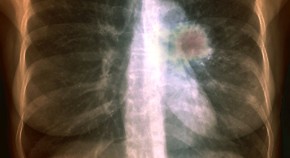

Advances in next generation sequencing have made it possible to precisely characterize the coding mutations that occur during the development and progression of individual cancers. Here, this technique is used to sequence the genomes and transcriptomes of an oestrogen-receptor-α-positive metastatic lobular breast cancer; significant evolution is found to occur with disease progression.

Tobacco smoke contains more than sixty carcinogens that bind and mutate DNA. Here, massively parallel sequencing technology is used to sequence a small-cell lung cancer cell line, exploring the mutational burden associated with tobacco smoking. Multiple mutation signatures from the cocktail of carcinogens in tobacco smoke are found, as well as evidence of transcription-coupled repair and another, more general, expression-linked repair pathway.

Here, the genomes of a malignant melanoma and a lymphoblastoid cell line from the same person are sequenced, providing the first comprehensive catalogue of somatic mutations from an individual cancer. The data provide insight into the causes of tumour formation and the development of the cancer genome, with the dominant mutational signature reflecting DNA damage due to ultraviolet light exposure.

Massively parallel DNA sequencing allows entire genomes to be screened for genetic changes associated with tumour progression. Here, the genomes of four DNA samples from a 44-year-old African-American patient with basal-like breast cancer were analysed. The samples came from peripheral blood, the primary tumour, a brain metastasis and a xenograft derived from the primary tumour. The findings indicate that cells with a distinct subset of the primary tumour mutation might be selected during metastasis and xenografting.